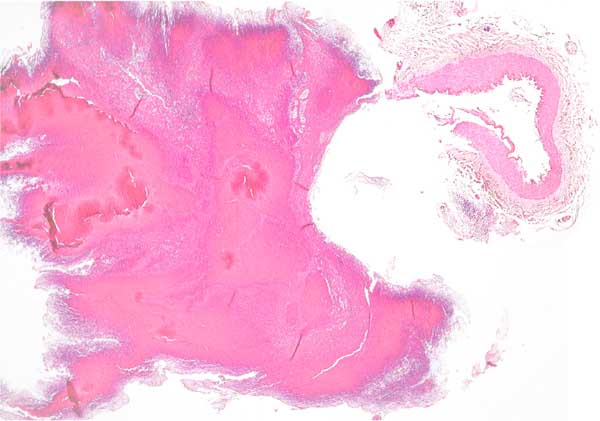

3. "Псевдоаневризмы" тоже описаны. Это образование мешкообразного выпячивания в толще кровяного тромба на месте свежего разрыва не изменённого сосуда. Отличаются от истинных только гистологически, так как стенка такой псевдоаневризмы состоит из слоёв кровяного сгустка (см. фото). У настоящей аневризмы есть хоть и тонкая, но стенка. На фото случай из клиники. После "пьяных разборок" около пивнушки в клинику был доставлен мужчина в безсознательном состоянии. Клиницисты увидели на компьютерном томографе БСаК и источник кровоизлияния, который они описали, как врождённую аневризму в области A. carotis interna. Через несколько дней мужчина не приходя в сознание умер. Переломов черепа не было. Труп попал к нам из-за этой истории. Мы нашли эту аневризму и исследовали её гистологически. Выяснилось, что это "псевдоанавризма" и разрыв сосуда был травматический. Сам сосуд на месте разрыва (как видно на фото справа)гистологически не изменён. "Аневризма состояла из тромба. Развилось вторичное кровотечение и мужчина умер от сдавления и отёка мозга. Это как бы дополнение к дискуссии по хроническим субдуральным гематомам. Хотя субдурально в нашем случае было мало крови.